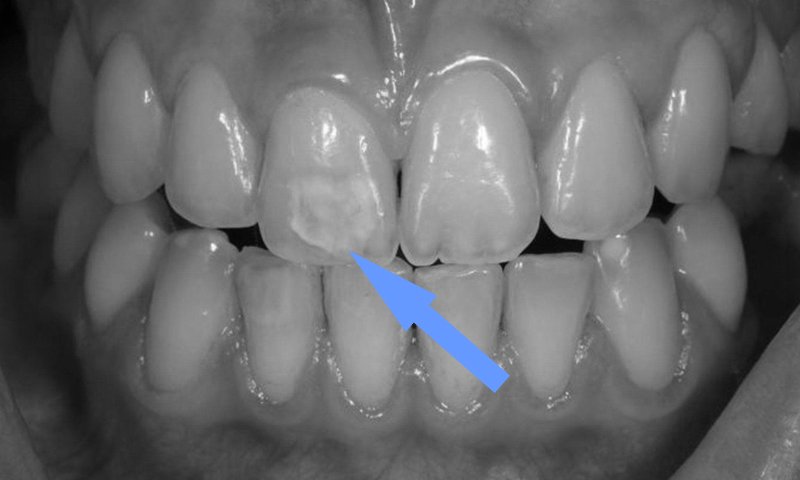

Entre as indicações da microabrasão dental como complemento da profilaxia está a remoção de manchas provocadas por hipoplasia do esmalte – manchas brancas cujas causas vão desde traumas ou febre elevado durante a formação do dente, na infância – ou a fluorose, esta causada pelo consumo excessivo de flúor durante a fase embrionária dos dentes.

A microabrasão dental, por outro lado, pode exigir várias consultas para casos mais severos de manchamento. Apesar de ser um procedimento seguro, a exposição prolongada do esmalte dentário à abrasão química e mecânica característica da técnica exige diagnóstico cuidadoso com relação à real efetividade na recuperação de dentes com alterações na estrutura do esmalte dentário.

A microabrasão dental pode ser combinada à limpeza dos dentes para remover manchas mais complexas.